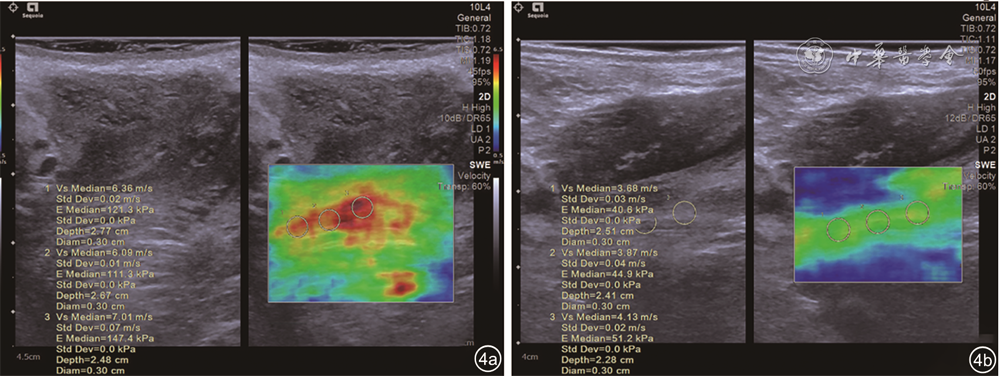

正常对照组和PFD组最大缩肛状态杨氏模量值及杨氏模量值差值比较,差异均有统计学意义(P均<0.05),2组静息状态杨氏模量值比较差异无统计学意义(P>0.05,表2图4)。

图 4 正常者(图a)和盆底功能障碍者(图b)耻骨直肠肌弹性图